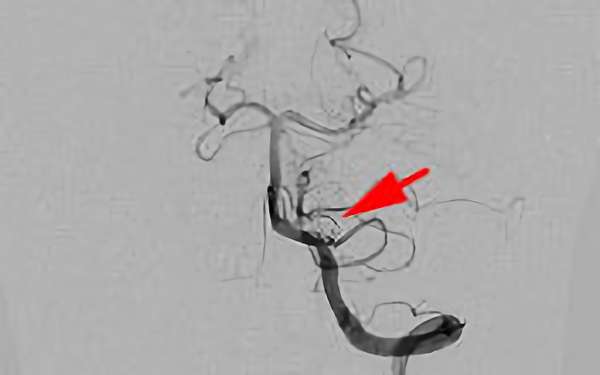

左椎骨動脈後下小脳動脈分岐部動脈瘤

70代

院内外来

No.1628 手術前

No.1628 手術中

No.1628 手術後